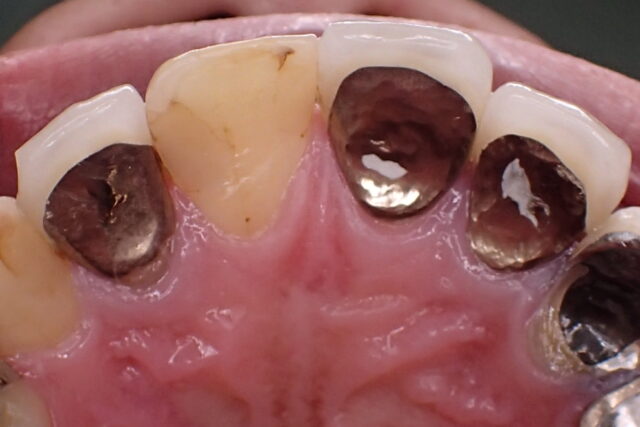

左右に大きく動いているため、

歯ぎしりの軌跡がX字を描くような

溝ができているパターンです。

奥歯を噛みしめながら、

その場で下顎が微妙に動いているケースです。

上顎前歯の結節部にも金属摩耗が見られます。

歯ぎしりで穴が空いた金属クラウン